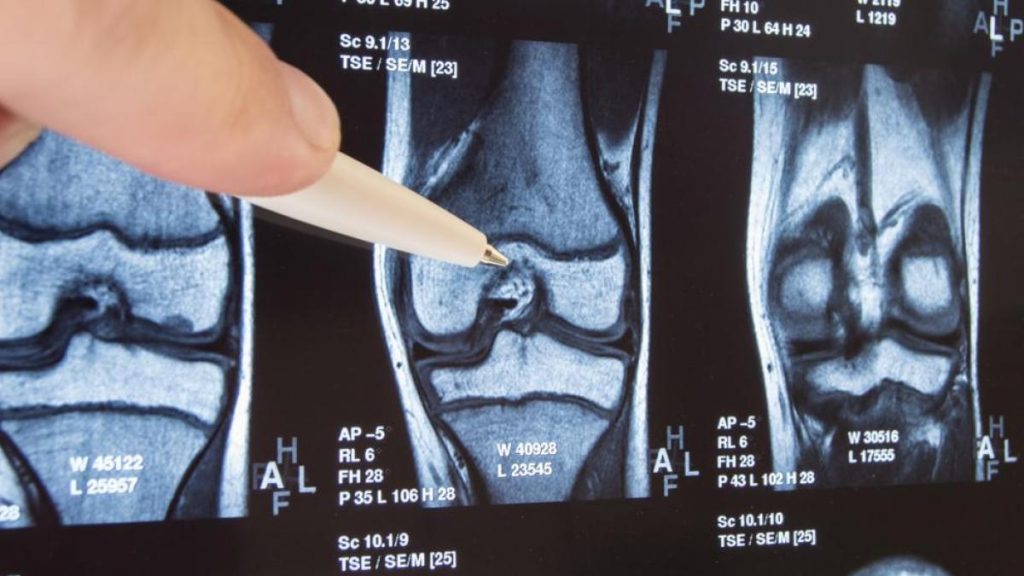

Los resultados más prometedores se obtuvieron en ratones con artrosis en las rodillas. Al inyectar el fármaco, las articulaciones se regeneraron y recuperaron su grosor adecuado.

El análisis de calidad del tejido mostró que el cartílago formado era del tipo hialino, permitiendo que los ratones tuvieran un buen grado de movilidad y una remisión del dolor.